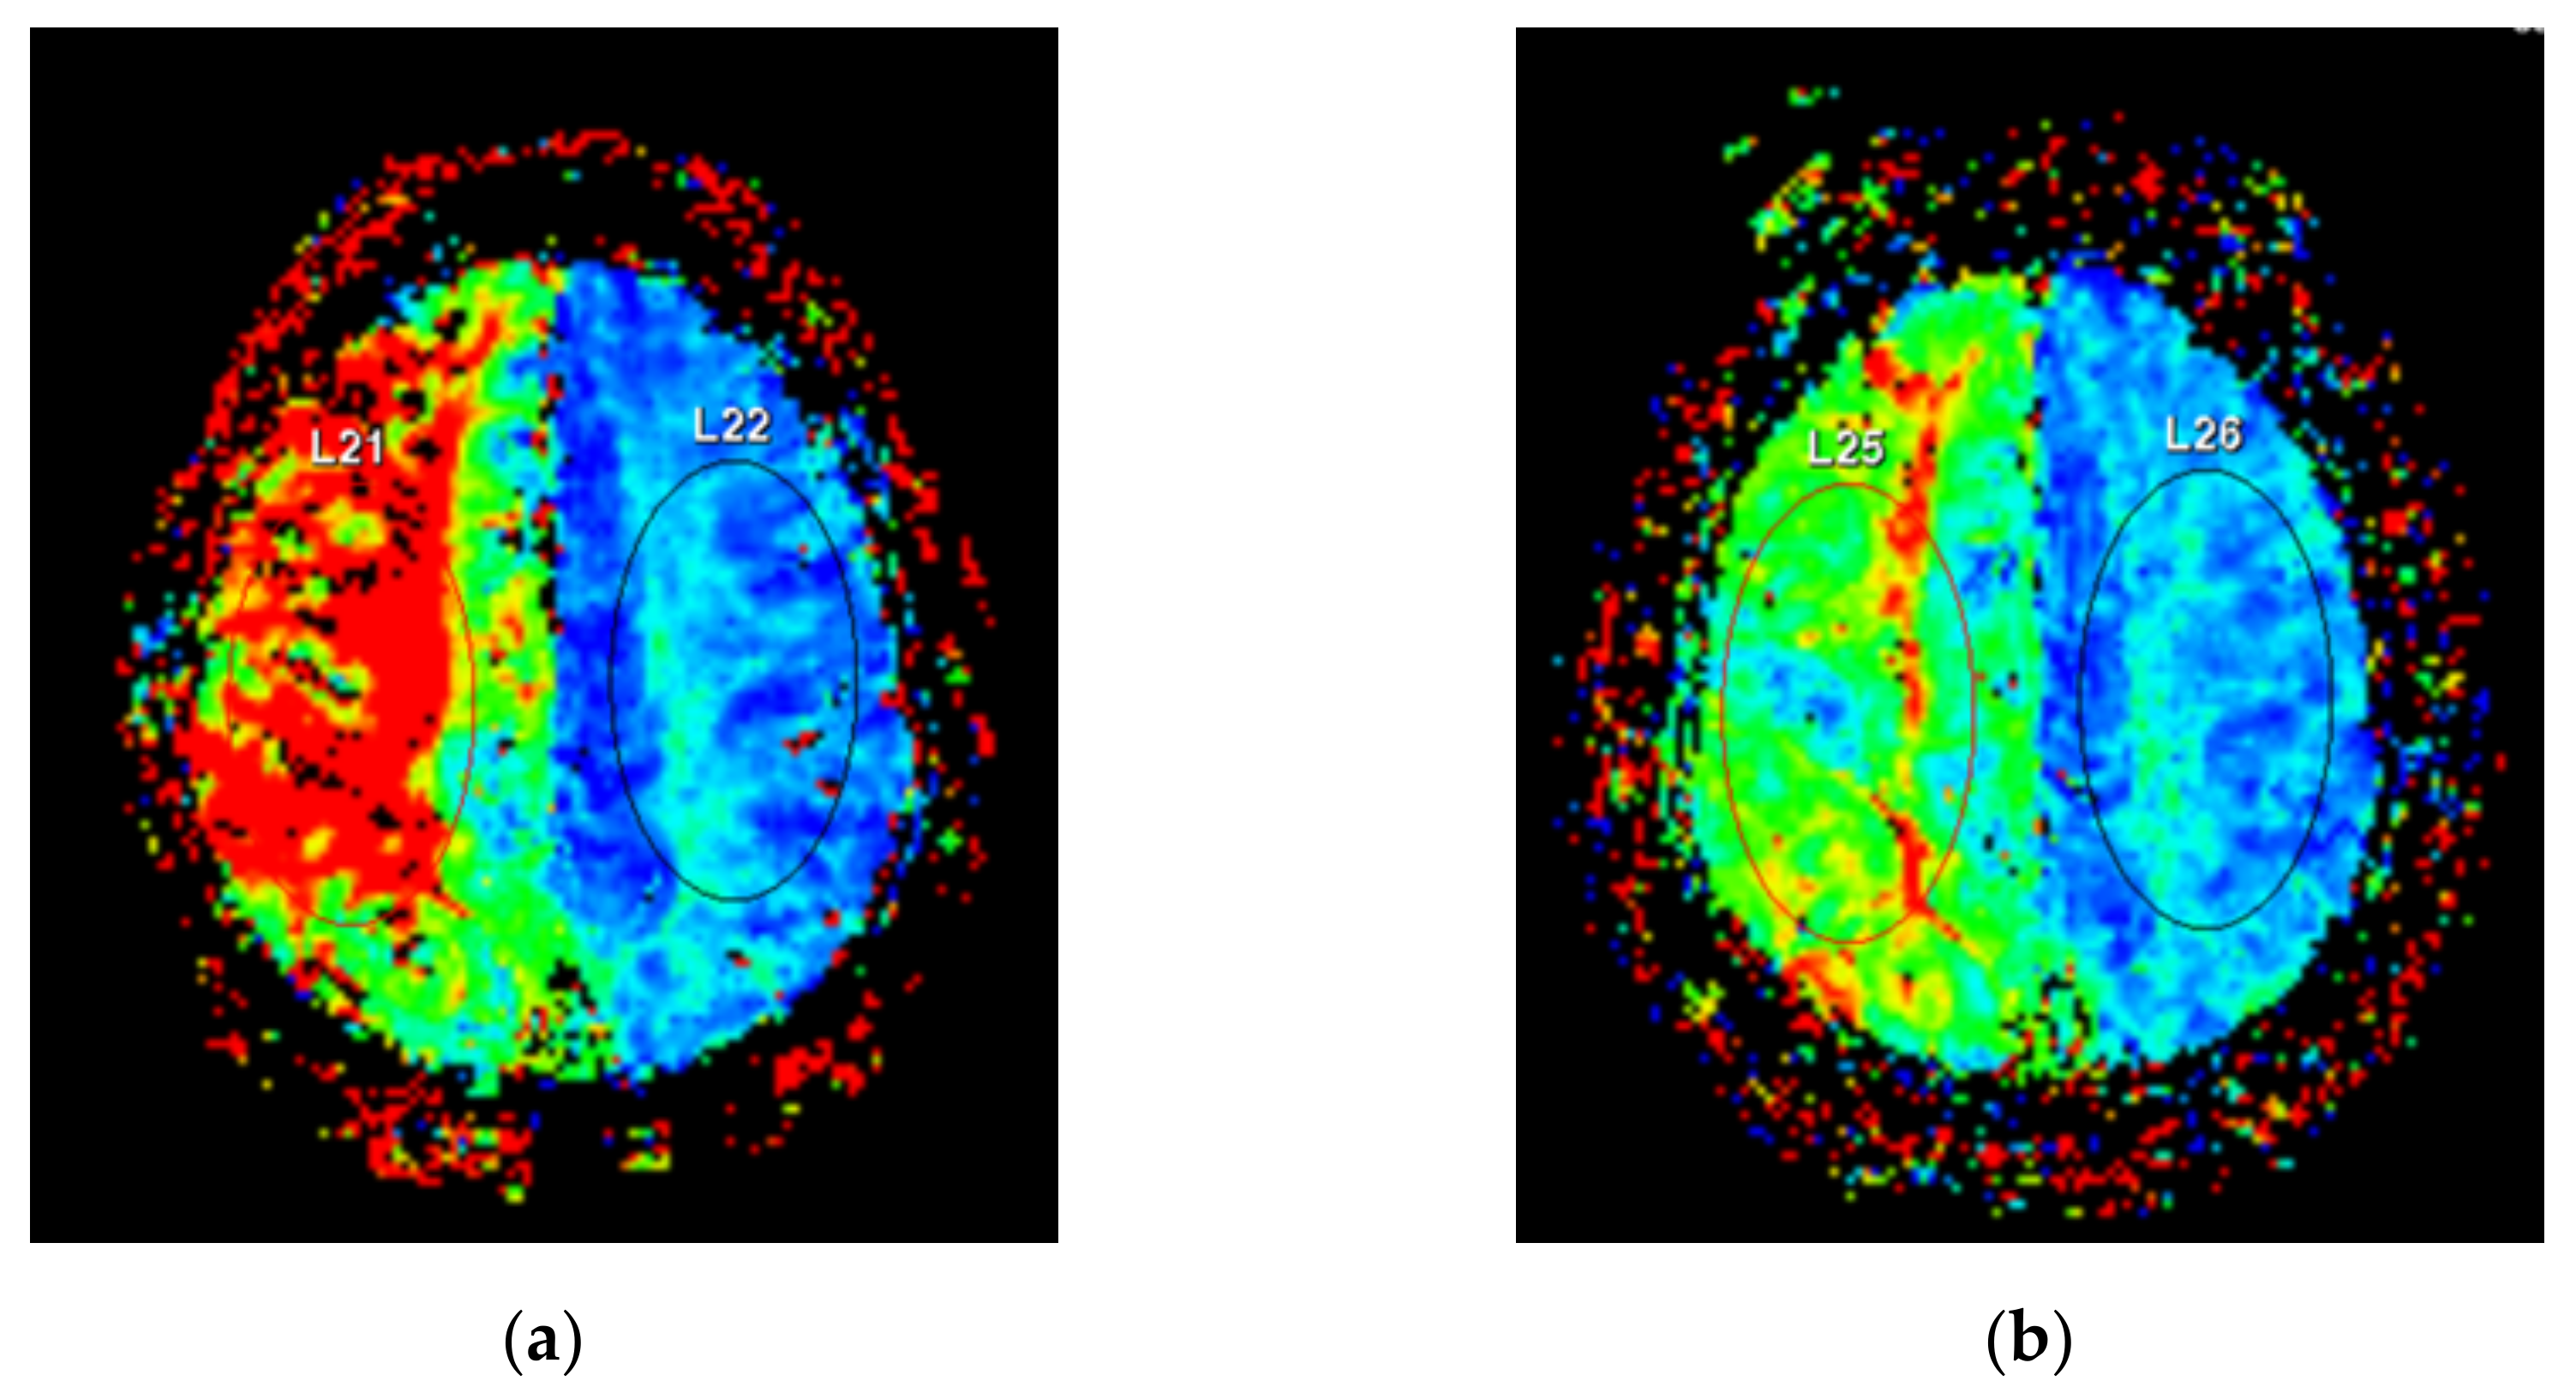

2.4. Perfusion-Weighted Imaging Protocol

ΔTTP = Preoperative TTP − Postoperative TTP

MTT AI = affected side MTT/unaffected side MTT

TTP AI = affected side TTP/unaffected side TTP

ΔMTT AI = ((Preoperative MTT AI − Postoperative MTT AI)/Preoperative MTT AI) × 100

ΔTTP AI = ((Preoperative TTP AI − Postoperative TTP AI)/Preoperative TTP AI) × 100